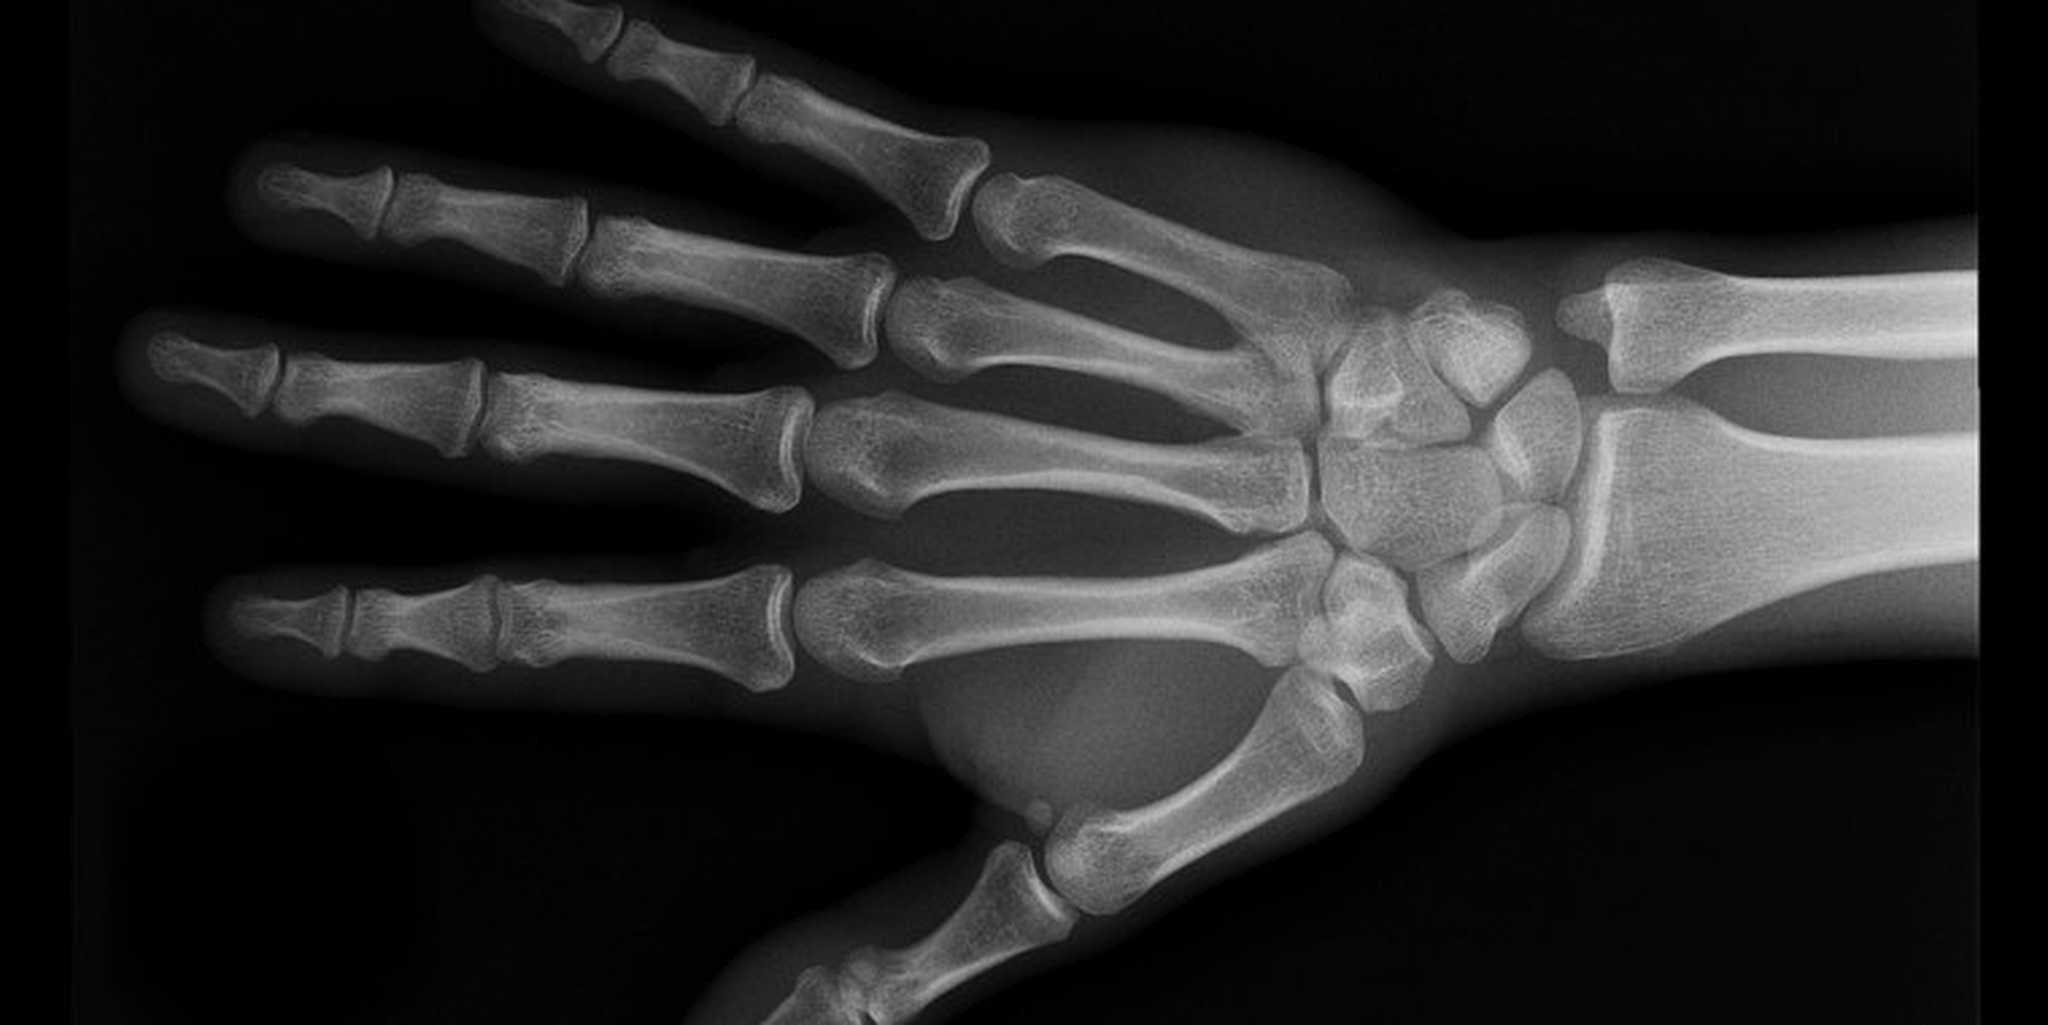

Hand

Not everyone has X-ray hardware lying around, so in order to get a beneath-the-skin glimpse of the human body, Drake collaborated with Weiss Orthopaedics of California. He then used Adobe Premiere and Photoshop to turn the video into animated GIFs, and the result is what you see below.

Getting an animated glimpse at the inner workings of the human body has never been easier thanks to a project by designer Cameron Drake. Using the Internet-borne art of the animated GIF, he's created a stunning set of moving X-ray images that are equal parts awesome and strange.